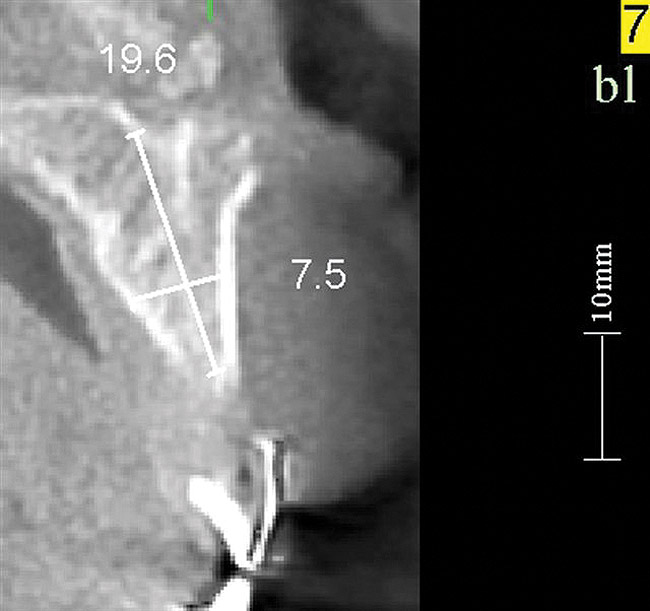

Volumetric imaging offers several advantages, including the 3-dimensional (3-D) assessment of the residual alveolar ridge, as well as sufficient resolution of the adjacent teeth to assess bone levels and periapical lesions. CBCT imaging offers access to volumetric imaging with the advantage over medical CT imaging of reduced radiation dose.10 A CBCT image permits the careful measurement of mesiodistal osseous dimension, buccolingual osseous dimension, and occlusogingival dimension of the alveolus, as well as the edentulous space (Figure 17 through Figure 19). The Rules of Six are readily interpreted from CBCT images. Using the Rules of Six, however, does not require that a CBCT image be produced.

Figure 17   Volumetric characterization of the residual alveolar ridge using CBCT: Fig 17 The coronal section of the maxilla reveals the cortical structure of the alveolar ridge associated with the missing right central incisor at the mid-root level. The buccal plate is identifiable and is characterized by little resorption. Fig 18  The saggital section of the maxillary alveolar ridge is displayed in relationship to the planned contour of the eventual implant crown. Fig 19 Importing DICOM files into planning software permits evaluation of the implant, abutment, and crown relationships with existing bone. These images readily characterize both the possible 6-mm mesiodistal width and the possible displacement of the implant 3-mm apical and 2-mm palatal to the planned gingival zenith.

Figure 18    Volumetric characterization of the residual alveolar ridge using CBCT: Fig 17 The coronal section of the maxilla reveals the cortical structure of the alveolar ridge associated with the missing right central incisor at the mid-root level. The buccal plate is identifiable and is characterized by little resorption. Fig 18  The saggital section of the maxillary alveolar ridge is displayed in relationship to the planned contour of the eventual implant crown. Fig 19 Importing DICOM files into planning software permits evaluation of the implant, abutment, and crown relationships with existing bone. These images readily characterize both the possible 6-mm mesiodistal width and the possible displacement of the implant 3-mm apical and 2-mm palatal to the planned gingival zenith.

Figure 19    Volumetric characterization of the residual alveolar ridge using CBCT: Fig 17 The coronal section of the maxilla reveals the cortical structure of the alveolar ridge associated with the missing right central incisor at the mid-root level. The buccal plate is identifiable and is characterized by little resorption. Fig 18  The saggital section of the maxillary alveolar ridge is displayed in relationship to the planned contour of the eventual implant crown. Fig 19 Importing DICOM files into planning software permits evaluation of the implant, abutment, and crown relationships with existing bone. These images readily characterize both the possible 6-mm mesiodistal width and the possible displacement of the implant 3-mm apical and 2-mm palatal to the planned gingival zenith.